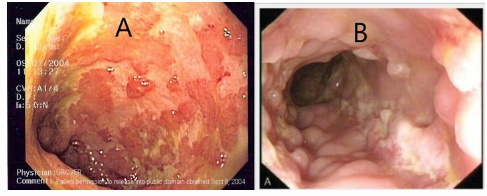

A- _____- Continuous involvement B - _____ - Cobblestone appearence